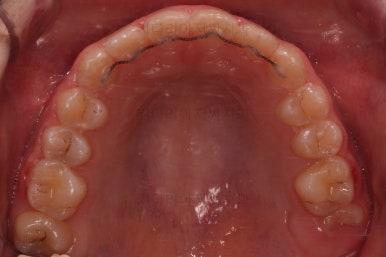

초진 시 입안의 모습입니다.

앞니가 안으로 굽어 들어간 양상인데요. 흔히 "옥니"라고 표현합니다.(뻐드렁니의 반대개념)

전반적으로 치열이 삐뚤삐뚤하고요.